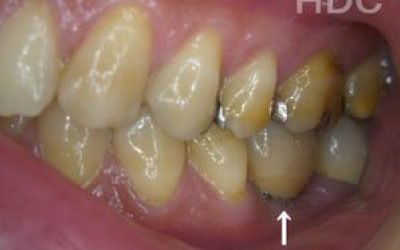

歯が抜けてそのままにしたら他の歯がズレてしまいました。どうしたらよいでしょう?

軽いズレなら調整や詰め物で対応できますが、大きく傾いた場合は矯正や被せ物が必要です。ズレが広がる前に早めの診査・治療をおすすめします。

多少の位置のズレであれば、噛み合わせの調整や小さい詰め物で調整することも出来ます。

ただ、抜けてから数年が経って大きく傾いた歯は歯並び矯正をするか、 歯を大きく削ってかぶせ物をする必要があります。

2 歯が傾いてくる、落ちてくる

歯の位置は互いに支え合ってバランスを保っています。 つまり、歯が抜けることによって支えが無くなり抜けた部分の両隣の歯が倒れたり、 上の歯が下がってきたりします。